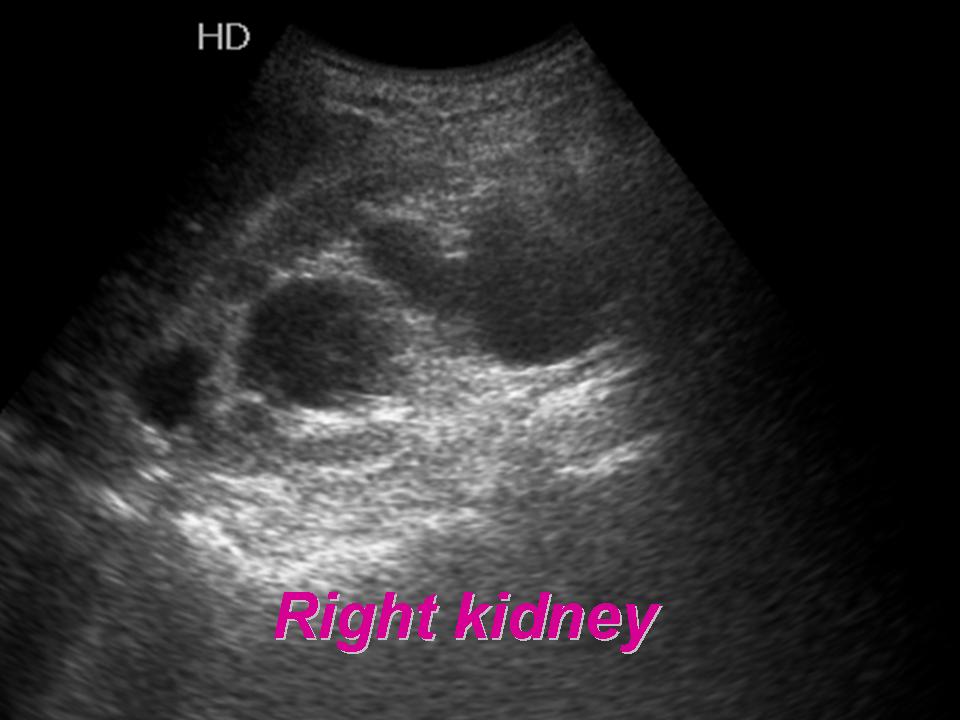

KUB ULTRASOUND l HYDRONEPHROTIC KIDNEY l NORMAL CBD AND PV l YouTube How To Perform Kub Ultrasound This blog post aims to provide a. Learn the basics of kidney and bladder ultrasound in just 5 minutes! Ultrasound is a test that uses sound waves to create an image of the inside of your body. In the male patient, the prostate. When healthcare providers use ultrasound to look at. Transabdominal ultrasound is a quick and easy modality to. How To Perform Kub Ultrasound.